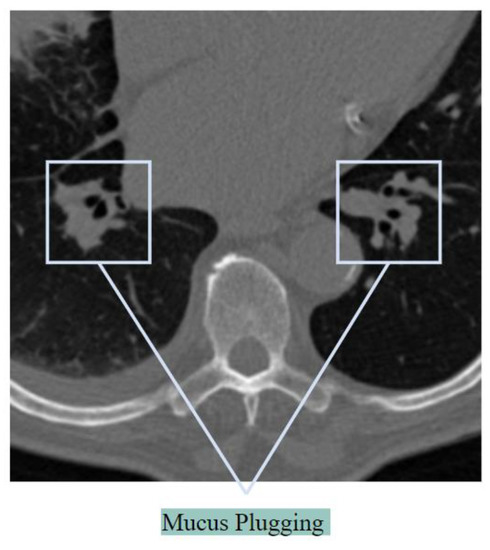

Mucus Plugging

The previously stated word ‘air bronchogram’ is sometimes regarded as incorrect as the bronchi are sometimes full of plugs of mucus, not with the air [28]. Mucus plugs in the bronchi cause a decrease in the bronchial diameter, impeding airflow [29]. Figure 7 illustrates mucus plugging.

Figure 7. Mucus plugging as seen in a CT scan.

Mucus that builds up in the lungs might plug up, or decrease airflow in, the greater or lesser airways. As the airways become smaller due to mucus plugs, it causes distorted alveoli. When a considerable number of alveoli are blocked, oxygen levels will decrease. Thick mucus in the bronchi may cause symptoms like a dry cough in patients having COVID-19 [30].